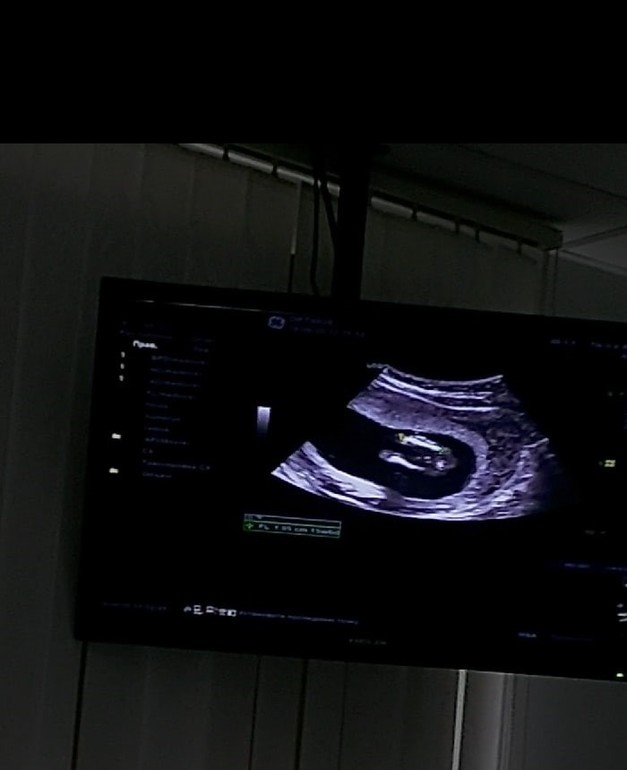

узи в 17 недель. Сказали пол ребенка!

Пол малышаВчера была на узи, сказали пол нашего ребеночка. У нас тадааам ДЕВОЧКА! Даже как-то не верится, на узи такая кааааак девочка?! И глаза квадратные😆 Всегда казалось что после двух девочек обязательно должен получиться пацан🤣

На узи переспросила несколько раз, точно девочка??? Мне развернули датчик и показали что между ножек пирожок😁 Вот честно, в упор смотрю и не вижу где там пирожок😆 Фото ниже для самых глазастых, а вы видите тут пирожок?😄